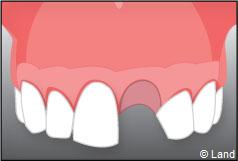

Exemple d’un implant unitaire pour remplacer une dent antérieure manquante.